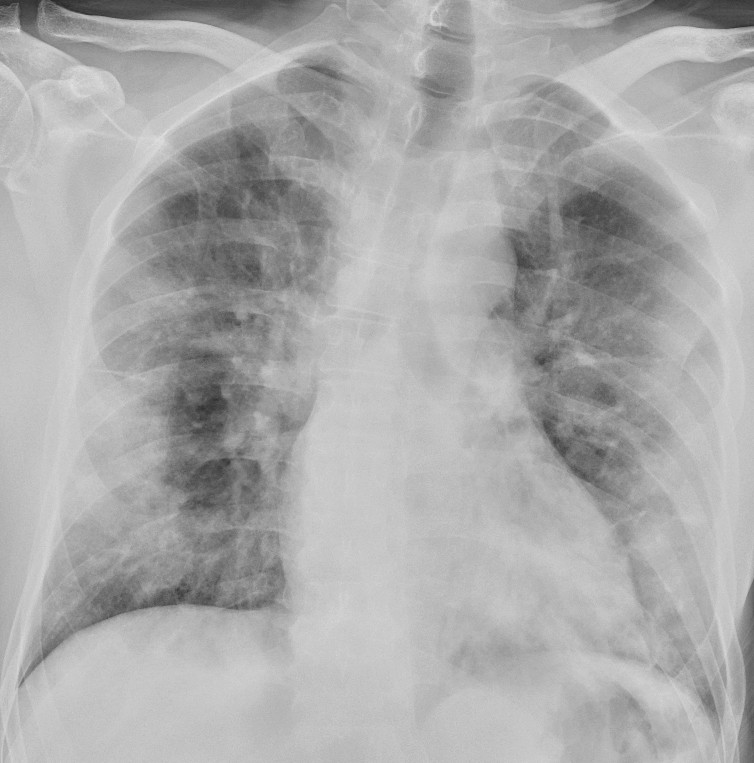

In a dataset from Hong Kong, 69 % had findings on chest X-rays prior to treatment (baseline), but 9 % had findings on chest X-ray prior to positive PCR (14). Sensitivity for chest X-ray was 69 % and for PCR 91 %. The most common X-ray findings were bilateral consolidation and ground-glass opacities with peripheral and caudal distribution. The findings were most pronounced 10–12 days after the onset of symptoms. Figures 1 and 2 show typical chest X-ray patterns in patients with COVID-19.

Patients with moderate symptoms should be evaluated for imaging in accordance with routines for other respiratory diseases. However, chest X-ray is not recommended as the primary modality for specific diagnosis of COVID-19 because a normal X-ray image does not rule out the disease and because typical findings are not specific enough to confirm it either. A chest X-ray may nonetheless be indicated with differential diagnosis in mind.

For inpatients, a bedside X-ray image at an early stage of the disease may be useful as a basis of comparison for interpreting later images. In patients with severe disease, bedside X-rays will be indicated to check technical medical equipment (Figure 3), but daily, routine chest X-rays are not indicated for stable patients. In the course of the disease, bedside X-ray will be indicated on suspicion of complications and for following up and monitoring the progression of the disease.